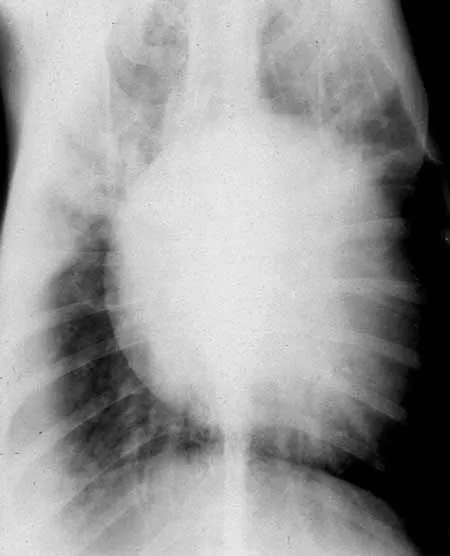

Siêu âm tim

Chụp X-quang ngực